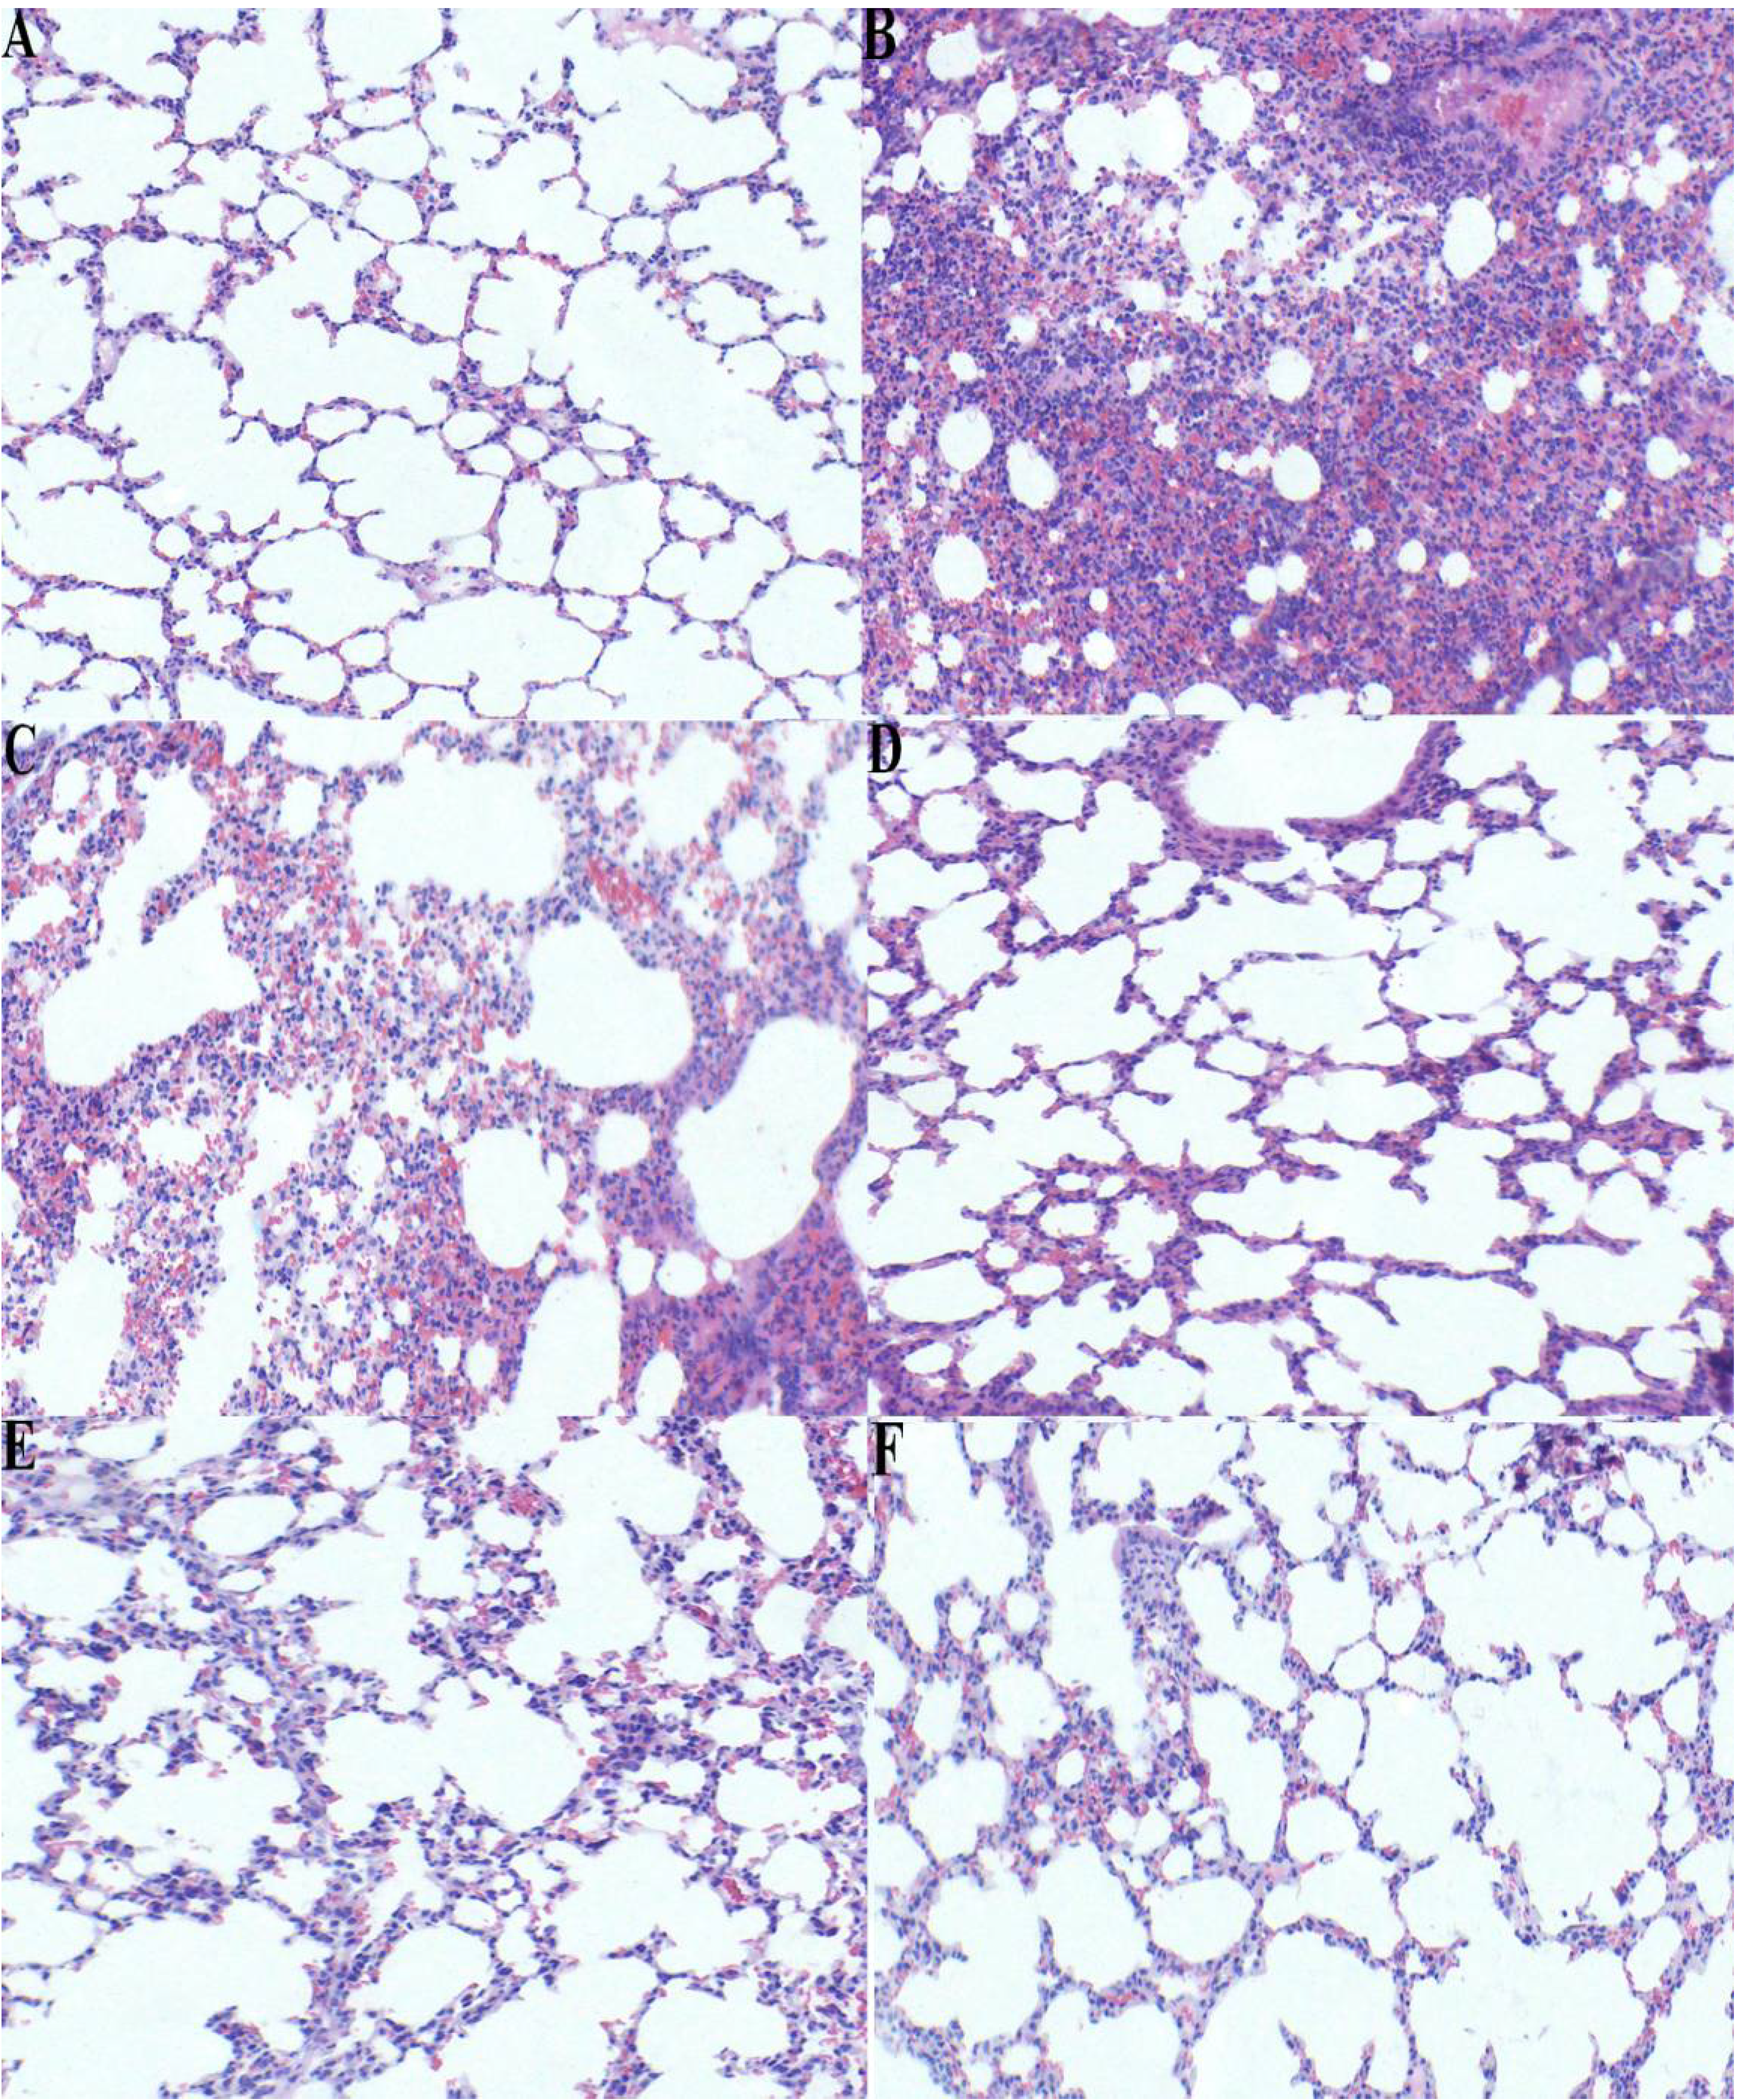

2.5. Effect of p-Cymene on Histopathological Changes in the Lung Tissue of LPS-induced ALI Mice